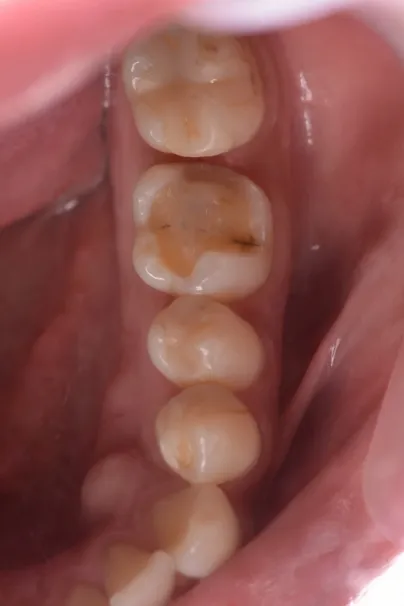

case3

Before

After

治療内容 | 右より、Zrクラウン、CTG+インプラント+Zrクラウン、ラミネートベニア(計3本修復)ホワイトニング |

---|---|

治療期間 | 8ヶ月 |

治療回数 | 15回 |

リスク | 外科的な侵襲、回数や期間的な問題 |

費用(税込) | ¥1,023,000 |